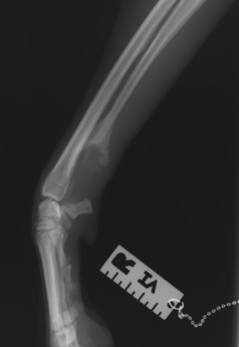

Osteosarkom je nejčastějším kostním nádorem u psa. Jedná se zhoubný nádor, tedy takový, který má schopnost metastázovat na jiná místa těla.